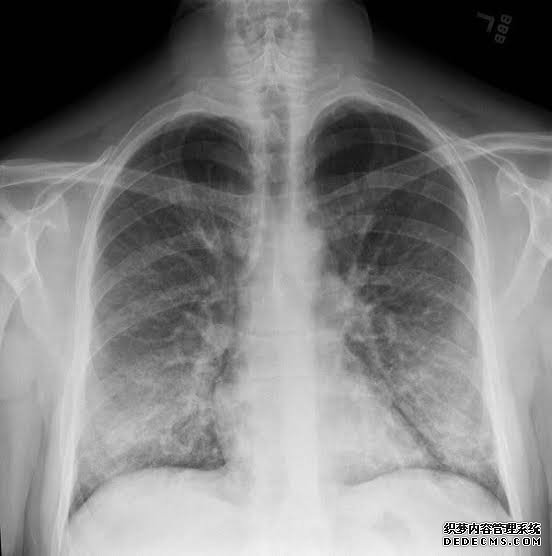

随着全国范围内的电子烟疫情持续扩大,已有近36人死于与电子烟有关的肺部疾病。

此前有报道称,官员们认为这些疾病背后可能存在“化学接触”。但目前还不清楚是什么化学物质或污染物造成的。美国疾病控制与预防中心(CDC)最近表示,含四氢大麻酚的产品可能在这些疾病中扮演重要角色,全国超过四分之三的患者报告使用了含有四氢大麻酚(大麻中的活性成分)的蒸汽产品。

美国疾病控制与预防中心表示,该中心目前正在对患者的肺活检和组织标本进行实验室检测,并对患者使用的电子烟产品进行“气溶胶排放测试”,以发现导致疫情爆发的化学物质。